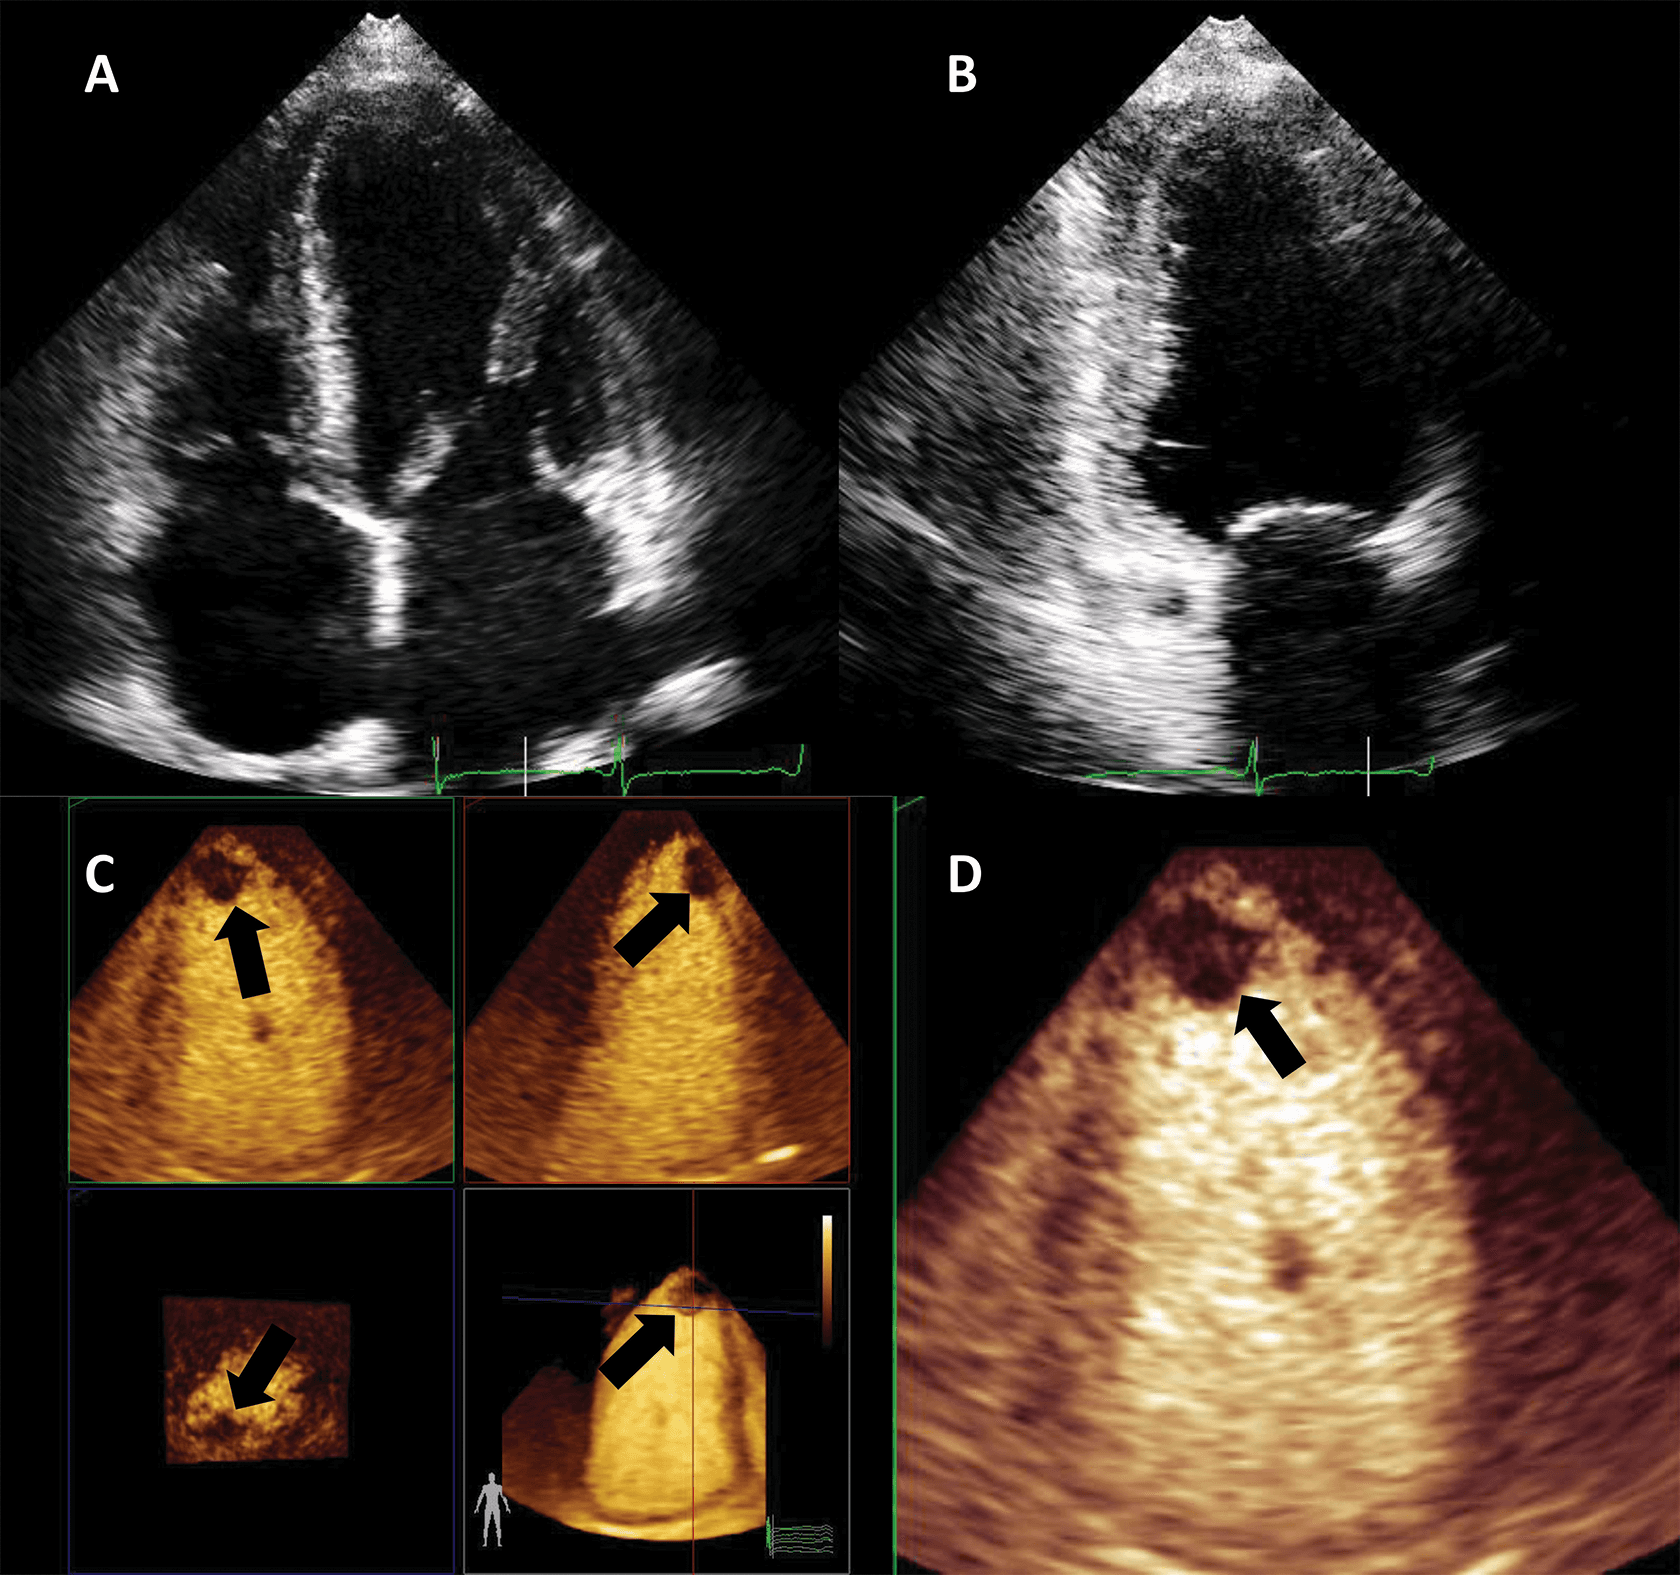

The addition of UEA during stress echocardiography protocols is usually achieved through an LVO application with low-MI harmonic imaging (Fig. 7, Video 6). The result is an increase in the likelihood of a diagnostic test, a better visualization of all myocardial segments, study quality and reader confidence, as compared to invasive or non-invasive reference [40, 41, 42, 43]. The addition of UEA to non-enhanced studies resulted in a better agreement with coronary angiography, even in patients with intermediate coronary lesions [44]. Of course, the use of LVO in stress echo has the largest impact in patients with suboptimal image [45]. Nevertheless, contrast-enhanced ultrasound also improves the wall motion score and detection of regional wall motion abnormalities in patients with adequate image quality [46]. Contrast-enhanced dobutamine stress echocardiography provided adequate risk stratification in patients with increased cardiovascular risk due to obesity or suspected coronary artery disease [47, 48, 49].

Fig. 7.Microbubble enhanced stress echocardiography. Baseline non-enhanced images are recorded in apical 4 and 2 chambers (A,B), demonstrating insufficient delineation of the endocardial borders; With contrast (C,D) the LV contours become clearly visible. Source: personal collection.

In patients with incomplete visualization of at least 2 contiguous segments contrast should be used for stress echocardiography. In patients with adequate image quality, contrast could be used to assess the myocardial perfusion, in addition to wall motion [7, 13].